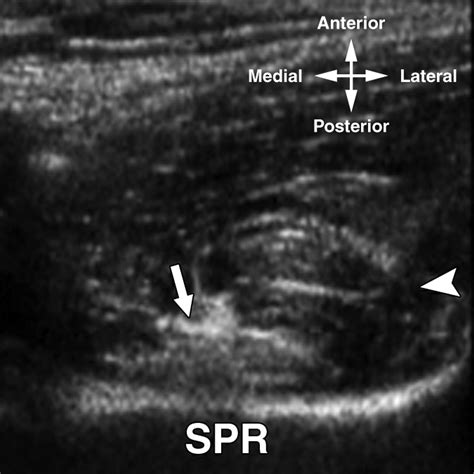

Snapping Hip Syndrome